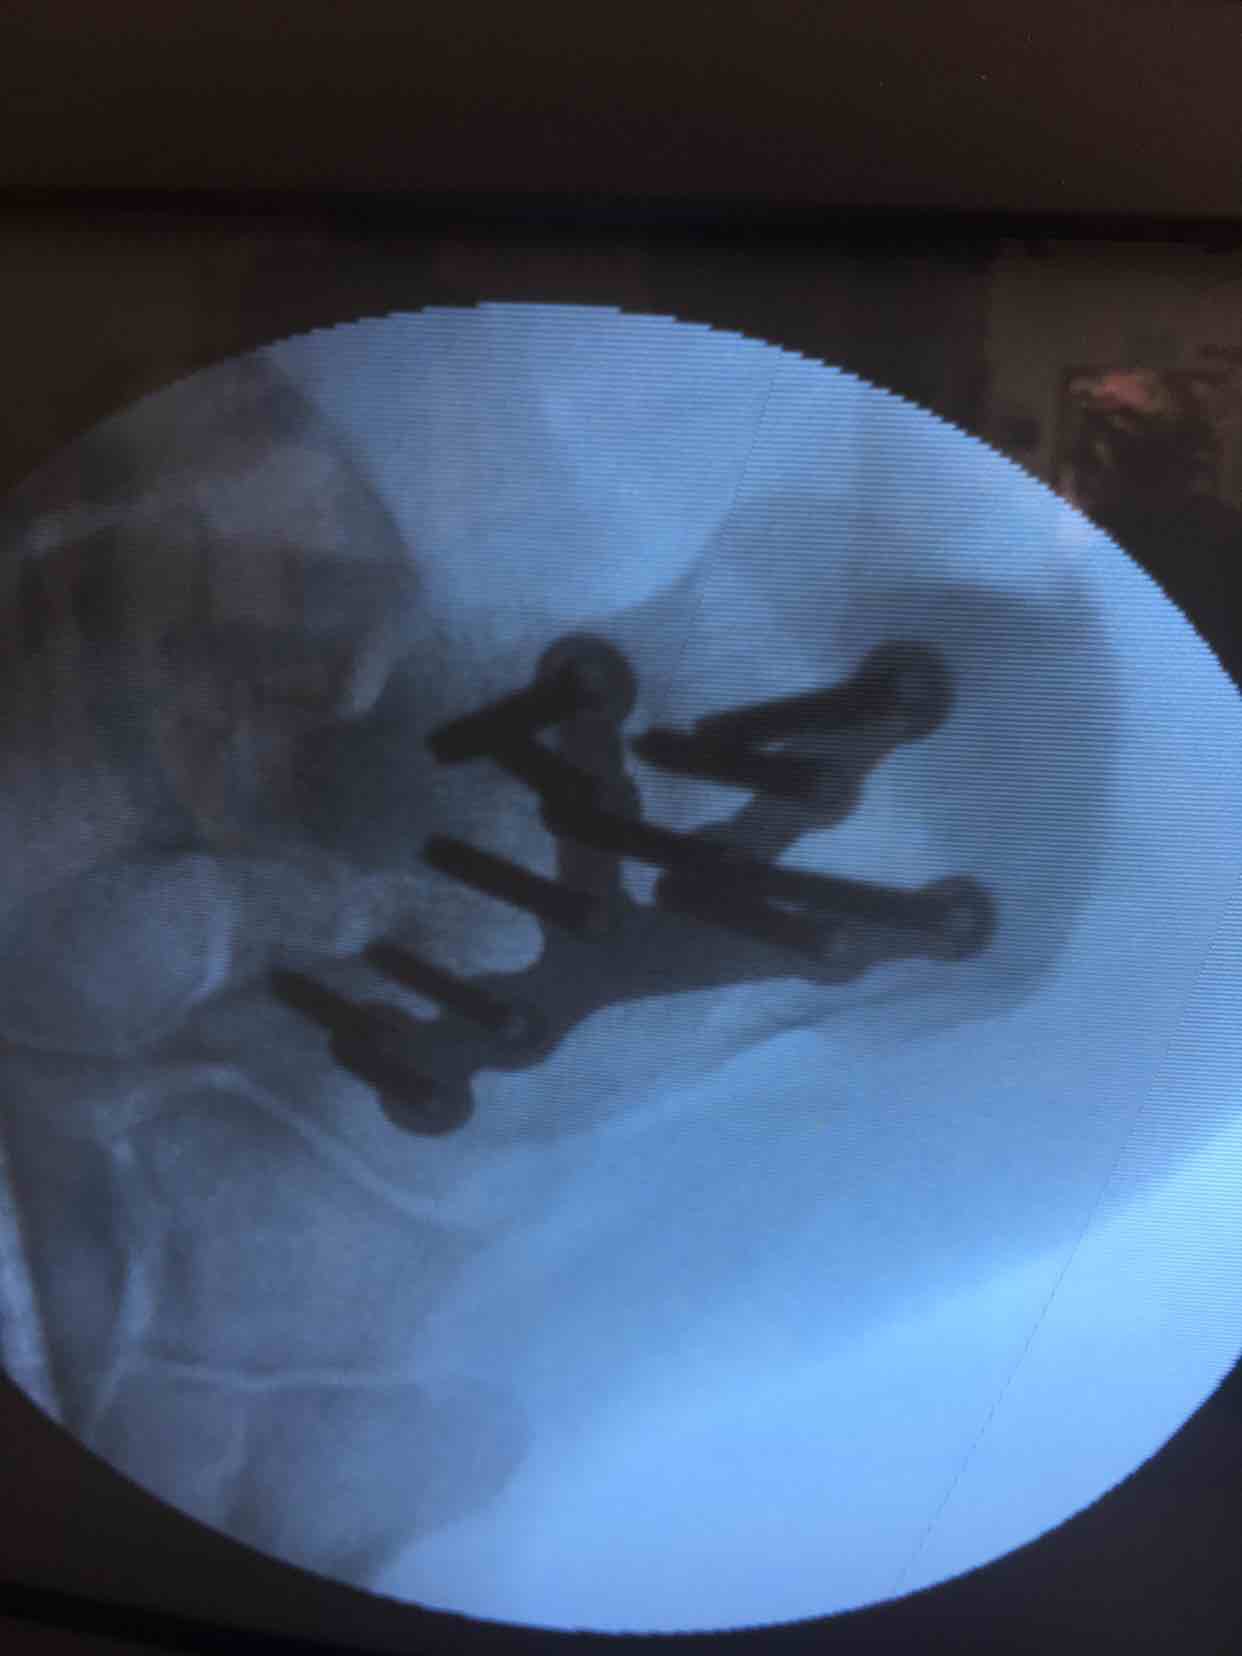

诊断  左跟骨粉碎性骨折完善术前检查,在腰麻下行切复内固定术,术中撬拨复位,选用克氏针临时固定,放置锁定钛板固定,术后抗炎,消肿等处理。